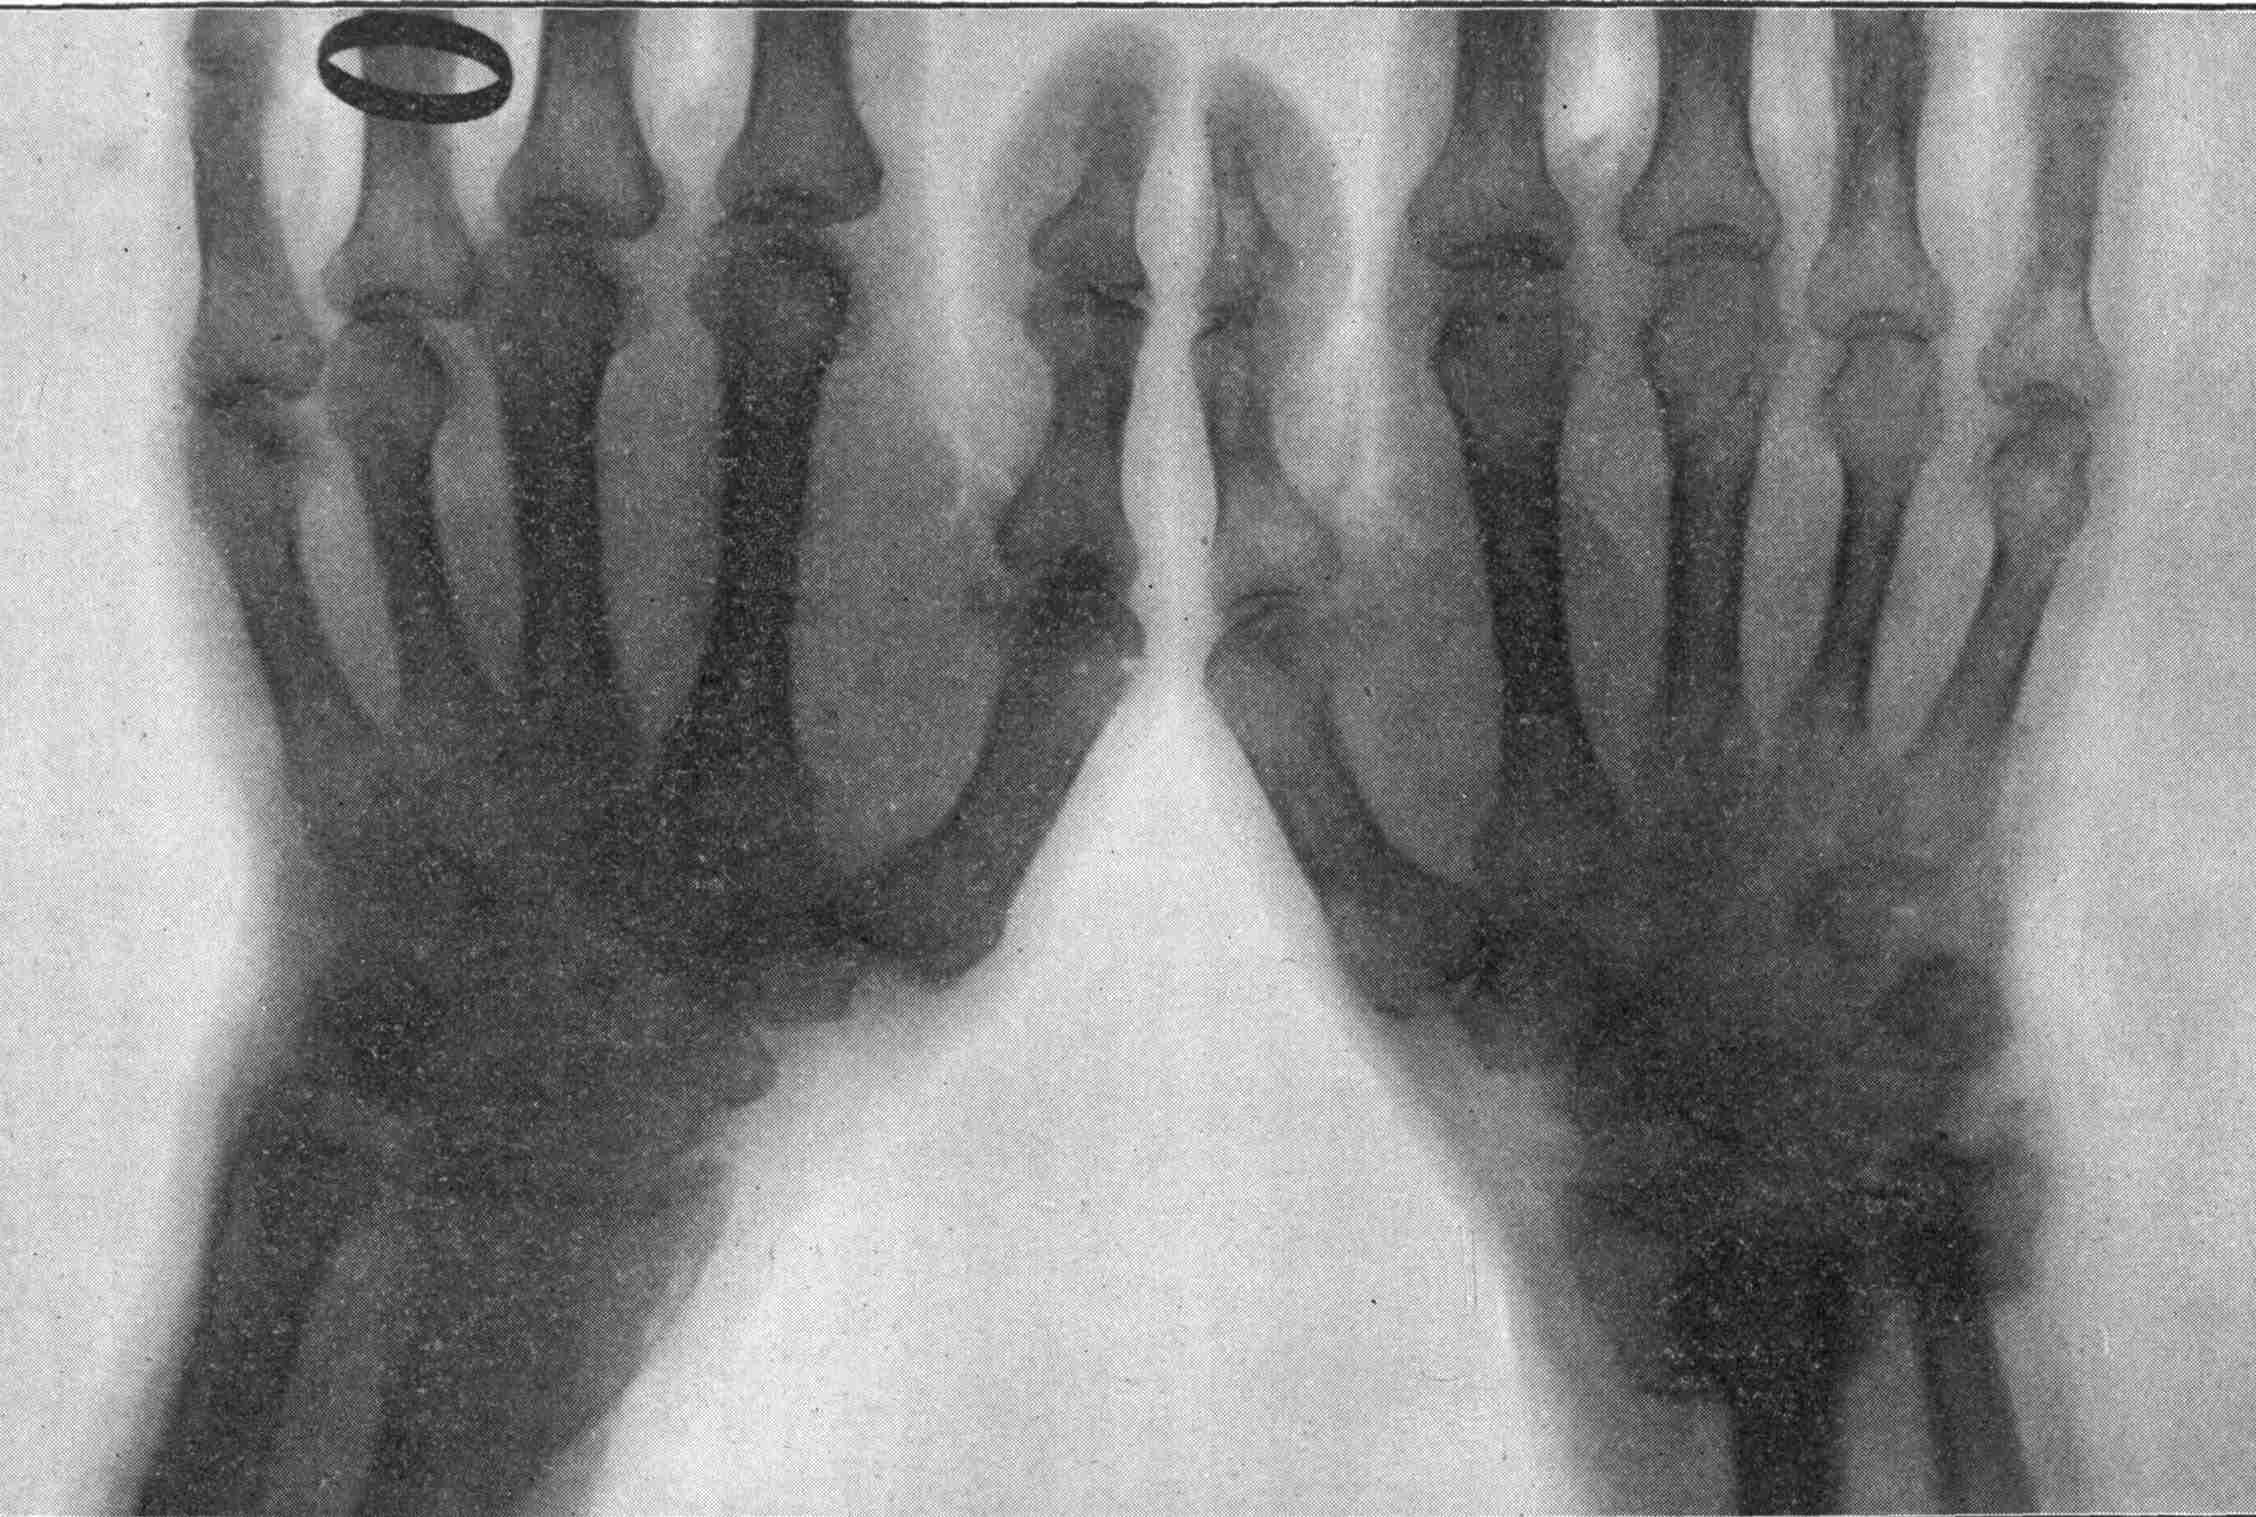

| 205. | Application of X-rays in Dentistry. | Morton |

| 207. | A Colles’ Fracture Detected by X-rays. | Morton |